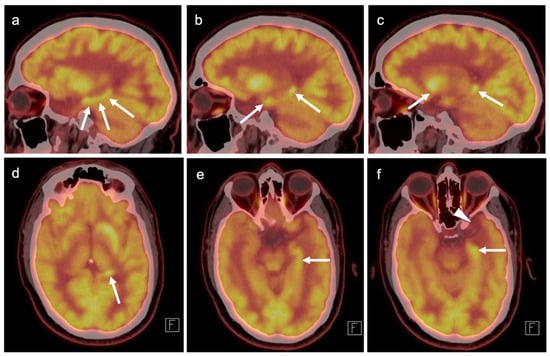

3.3. Primary Brain Tumors

3.4. CNS Lymphoma

3.5. Brain Metastases

3.6. Response to Therapy